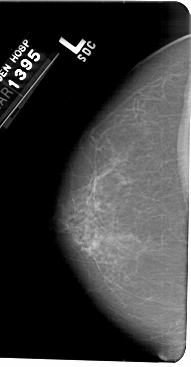

A_1405_1.RIGHT_MLO

RIGHT_MLO LINES 5491 PIXELS_PER_LINE 2941 BITS_PER_PIXEL 12 RESOLUTION 43.5 OVERLAY

FILE: A_1405_1.RIGHT_MLO.OVERLAY

TOTAL_ABNORMALITIES 1

ABNORMALITY 1

LESION_TYPE MASS SHAPE LOBULATED MARGINS ILL_DEFINED

ASSESSMENT 3

SUBTLETY 3

PATHOLOGY BENIGN